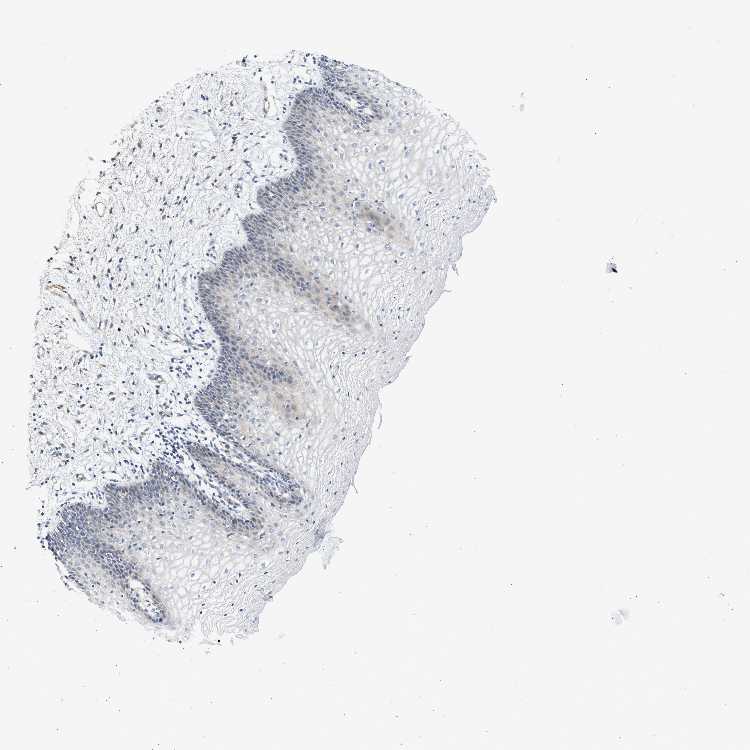

VAGINA - Antibody stainingi

Antibody staining in the annotated cell types in the current human tissue is reported as not detected, low, medium, or high, based on conventional immunohistochemistry profiling in selected tissues. This score is based on the combination of the staining intensity and fraction of stained cells.

Each image is clickable and will lead to virtual microscopy that enables deeper exploration of all samples and also displays staining intensity scores, fraction scores and subcellular localization as well as patient and tissue information for each sample.

Antibody HPA001040Antibody HPA001391Antibody CAB020817

Squamous epithelial cells Not detectedNot detectedNot detected